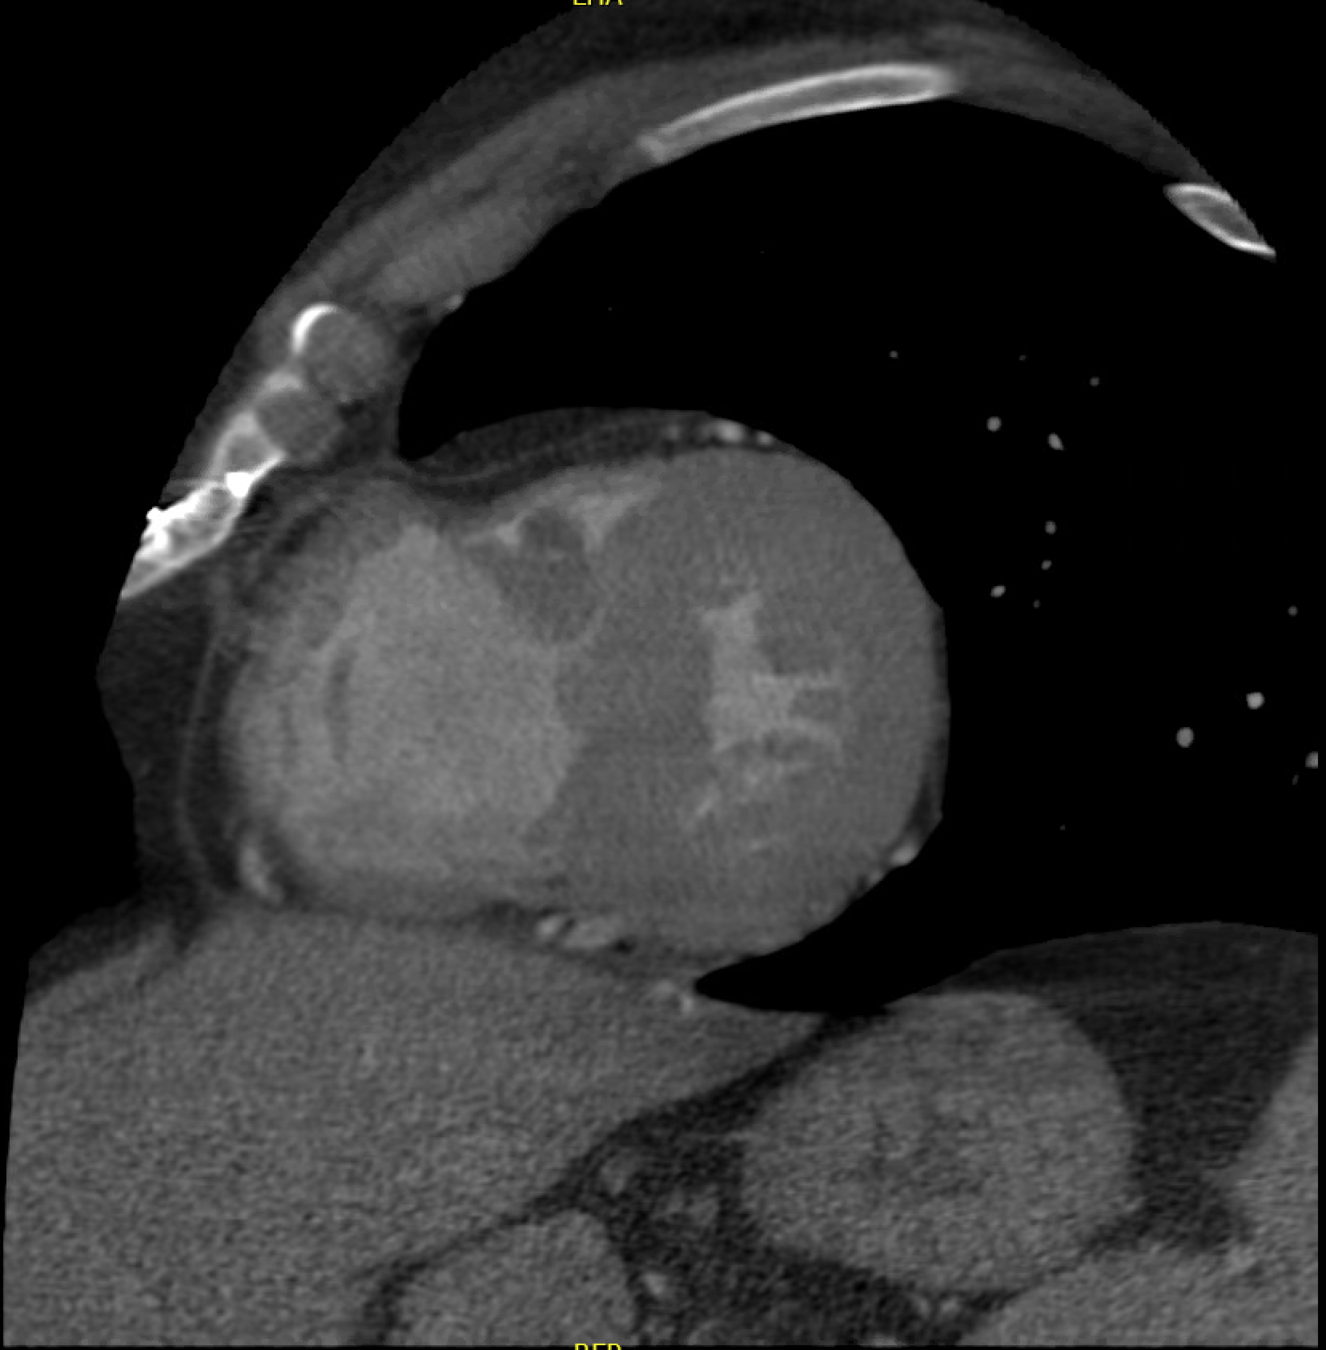

Mitral Aortic Intervalvular Fibrosa MAIF

Fibrous region of the heart that connects the anterior mitral leaflet to the posterior aortic root and communicates with the left ventricular outflow tract

MAIF Pseudoaneurysm